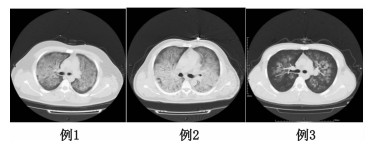

3例患者均为男性,年龄21~45岁,平素体健,化工厂工人。工作中接触泄漏的有机氟气体八氟异丁烯后咳嗽气喘约8 h于2014年11月13日来我院急诊 (患者均为车间工作,具体接触原因不详,大约接触7 h后首先出现咳嗽症状)。来院时均有不同程度的胸闷、气急,并且开始出现恶心、呕吐等症状。查体:GCS 14~15分,HR 110~140次/min,平均动脉压 (MAP) 65~75 mmHg (1 mmHg=0.133 kPa),呼吸 (R) 35~40次/min,双肺呼吸音粗,可闻及广泛湿啰音,心律齐。血气分析:PCO2 30~39 mmHg,PO2 51~73 mmHg,氧合指数 (PO2/FiO2):150~195 mmHg,肺CT示:两肺片状模糊影,广泛渗出 (图 1)。根据职业性急性有机氟中毒诊断标准 (GBZ66-2002)[6]和ARDS柏林标准[7-8]诊断:急性有机氟气体吸入中毒、急性呼吸窘迫综合征 (ARDS)。均按分诊分级标准分为Ⅰ级,经绿色通道收入重症监护室 (intensive care unit, ICU),首日APACHEⅡ评分为19~26分。24 h后复查肺CT进展迅速 (图 2)。

图 2 3例患者24 h后复查肺CT检查结果